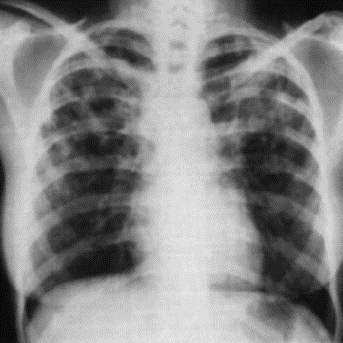

1.2.1 Radiografia (tomografia, broncografia)

Metodo diagnostico prevalente, eventualmente completato con tomogramma delle parti dubbiose o broncografia (a contrasto).

Con radiografia.

Con radiografia, analisi sputo (cellule cancerogene), scintigrafia e broncoscopia.

Sputo, radiografia, test di tubercolina.